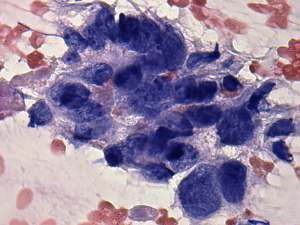

Cytological diagnosis: anaplastic carcinoma.

Histopathology: anaplastic carcinoma.